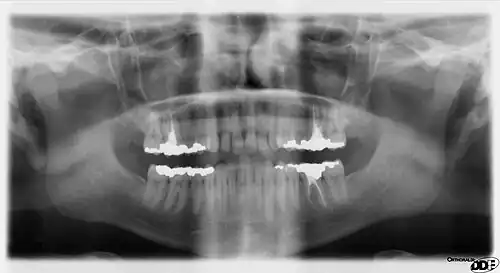

A panoramic radiograph is a panoramic scanning dental X-ray of the upper and lower jaw. It shows a two-dimensional view of a half-circle from ear to ear. Panoramic radiography is a form of focal plane tomography; thus, images of multiple planes are taken to make up the composite panoramic image, where the maxilla and mandible are in the focal trough and the structures that are superficial and deep to the trough are blurred.

Normally, the person bites on a plastic spatula so that all the teeth, especially the crowns, can be viewed individually. The whole orthopantomogram process takes about one minute. The patient's actual radiation exposure time varies between 5.5 and 22 seconds for the machine's excursion around the skull.

The collimation of the machine means that, while rotating, the X-rays project only a limited portion of the anatomy onto the film at any given instant but, as the rotation progresses around the skull, a composite picture of the maxillo-facial block is created. While the arm rotates, the film moves in a such way that the projected partial skull image (limited by the beam section) scrolls over it and exposes it entirely. Not all of the overlapping individual images projected on the film have the same magnification because the beam is divergent and the images have differing focus points. Also not all the element images move with the same velocity on the target film as some of them are more distant from and others closer to the instant rotation center. The velocity of the film is controlled in such fashion to fit exactly the velocity of projection of the anatomical elements of the dental arch side which is closest to the film. Therefore, they are recorded sharply while the elements in different places are recorded blurred as they scroll at different velocity.